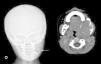

Con la sospecha diagnóstica de granuloma eosinófilo contra sarcoma de partes blandas, es remitido a su hospital de referencia para completar estudio y tratamiento. La tomografía computarizada (TC) mostró una lesión lítica, muy expansiva, en el ángulo y la rama ascendente de la mandíbula izquierda, con aspecto loculado y límites óseos preservados pero muy adelgazados. En la fase vascular había captación de contraste muy tardía y heterogénea, sin masa de partes blandas (fig. 2). El estudio histológico de la pieza biópsica evidenciaba una neoformación no productora de hueso, constituida por fibroblastos inmersos en una matriz de fibras de colágeno. La densidad celular era variable según el campo estudiado, al igual que la disposición de las fibras de colágeno. Las células tenían núcleos ovoideos, sin nucléolos, figuras mitóticas ni atipias.

Los hallazgos radiográficos son inespecíficos, se objetiva una lesión transparente, unilocular o multilocular, bien delimitada o algo irregular en su contorno, que puede tener un aspecto trabeculado como en «panal de abejas» y dar una imagen de «diente flotante» que, aunque indicativa, no es exclusiva de este tipo de tumor y localización2,7,8. En la radiología, por su aspecto expansivo, puede simular un fibrosarcoma2 e incluso ser difícil su distinción histológica en caso de fibrosarcomas de bajo grado4. La TC es útil para determinar la continuidad de la cortical del hueso, la invasión de partes blandas y la presencia de matriz ósea en su interior.